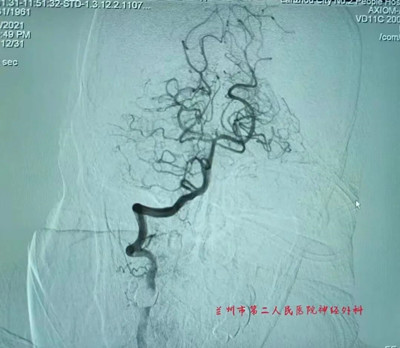

术后复通的基底动脉